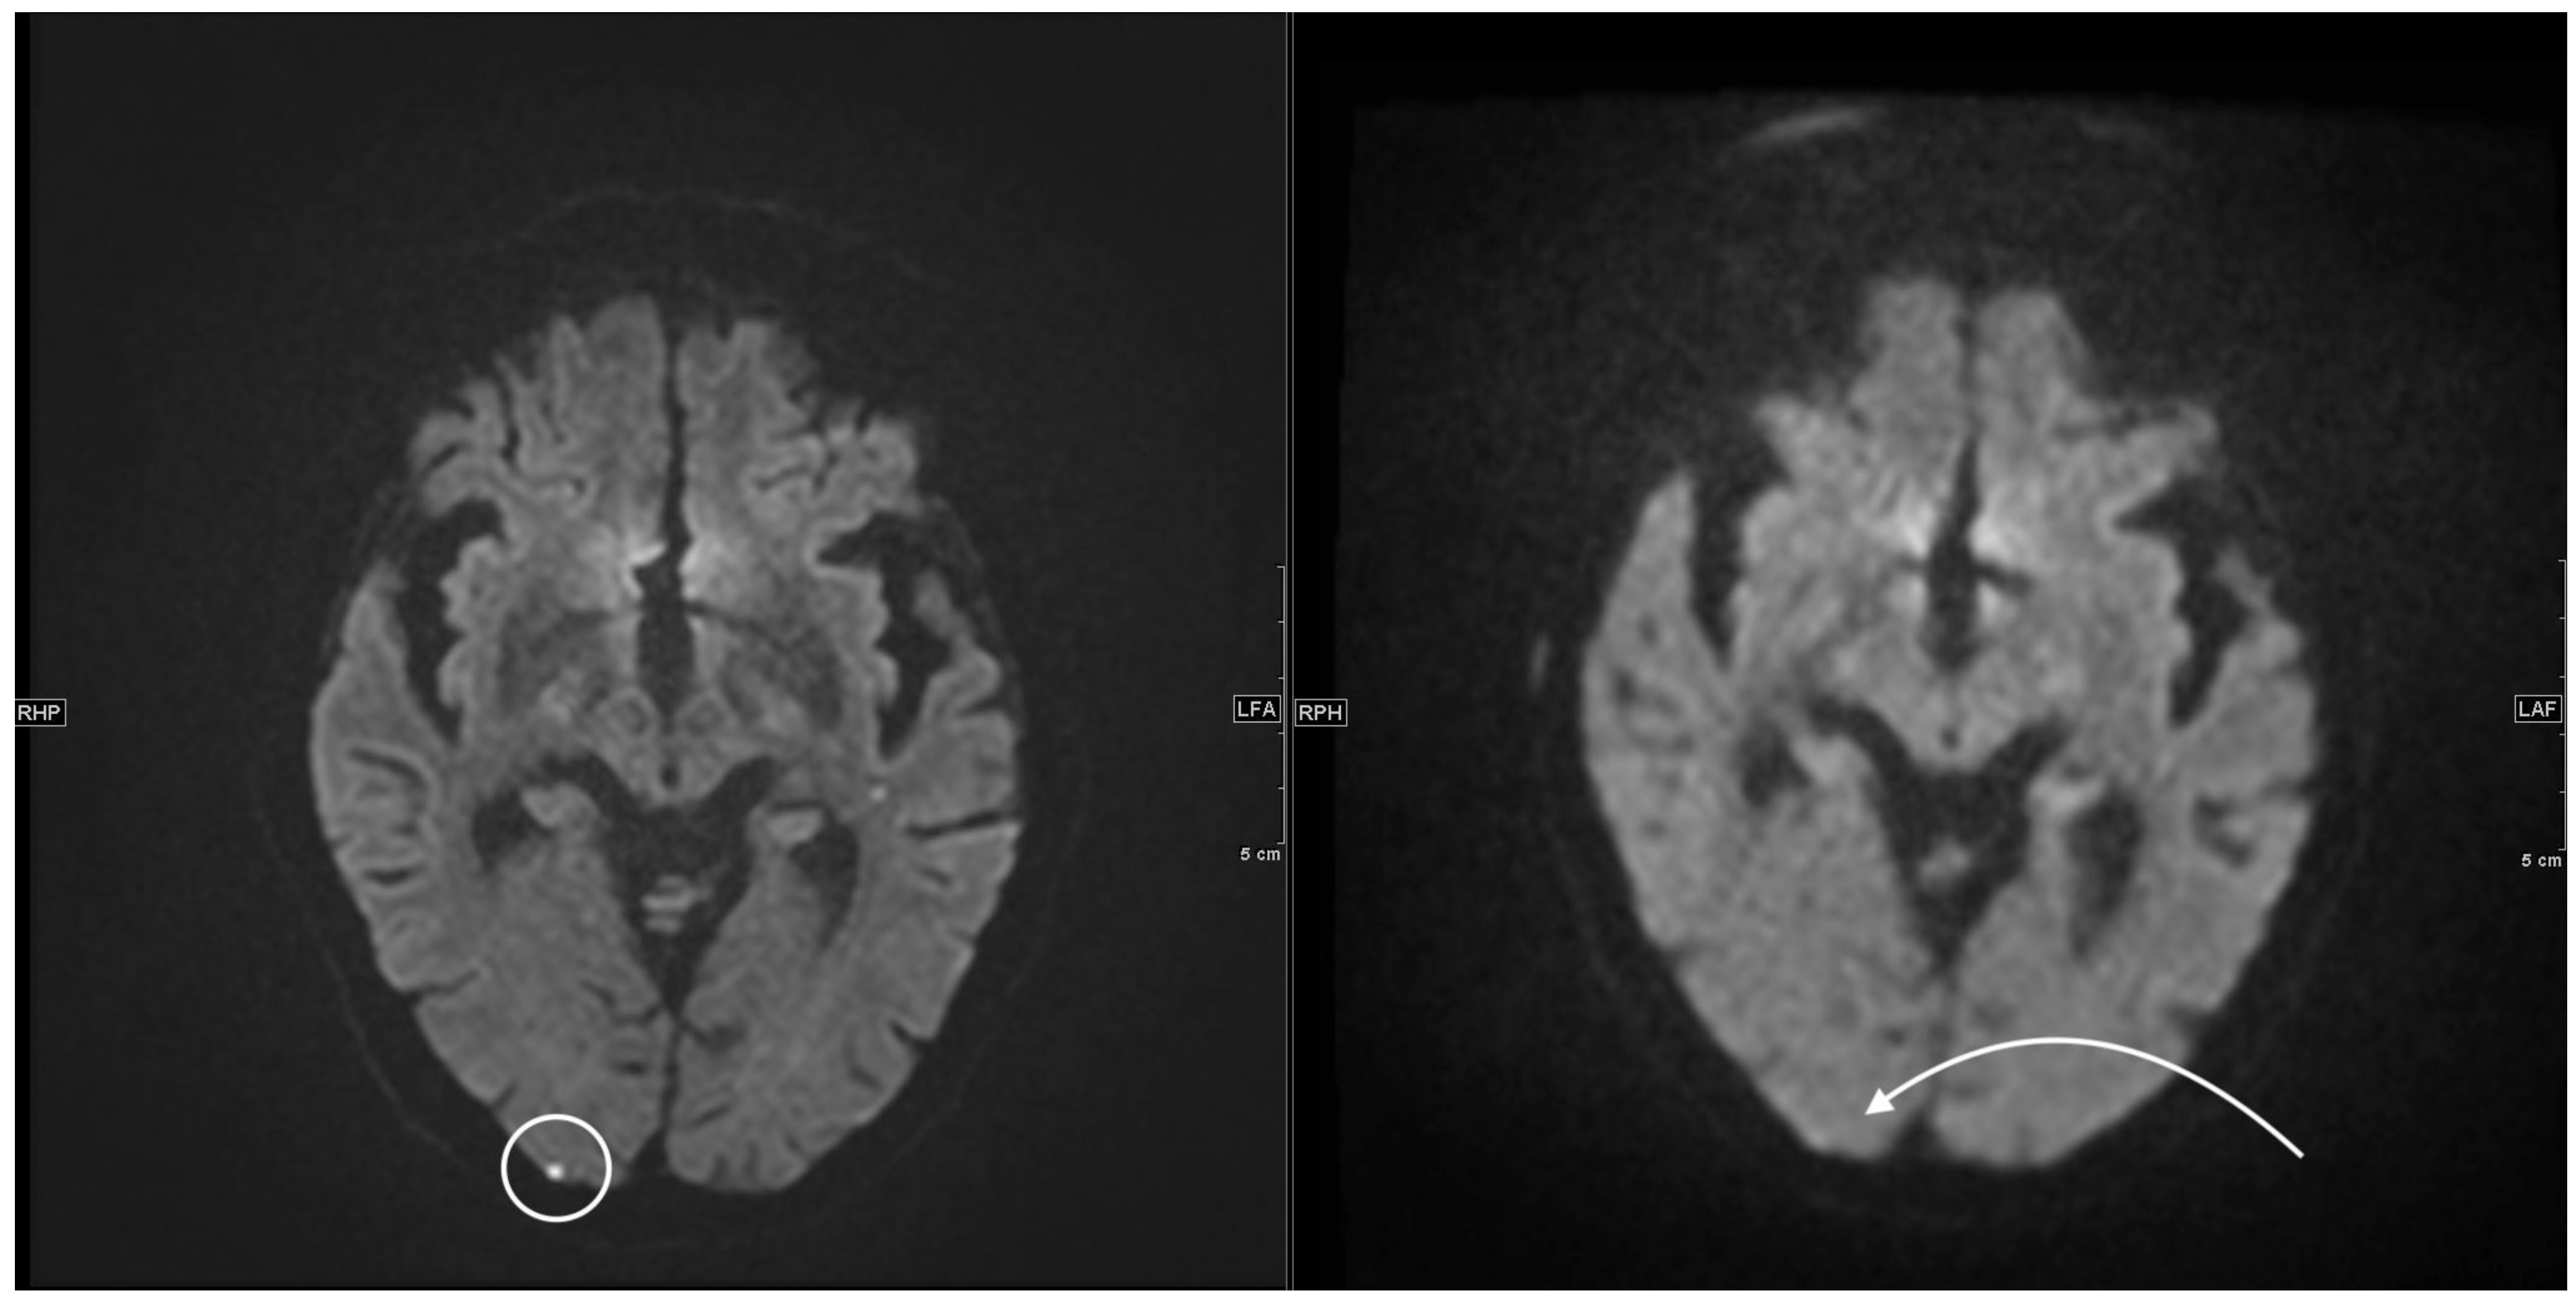

3.2. Reading Study

3.2.1. DWI/ADC Datasets

3.2.2. FLAIR Datasets

4. Discussion

Reading Study